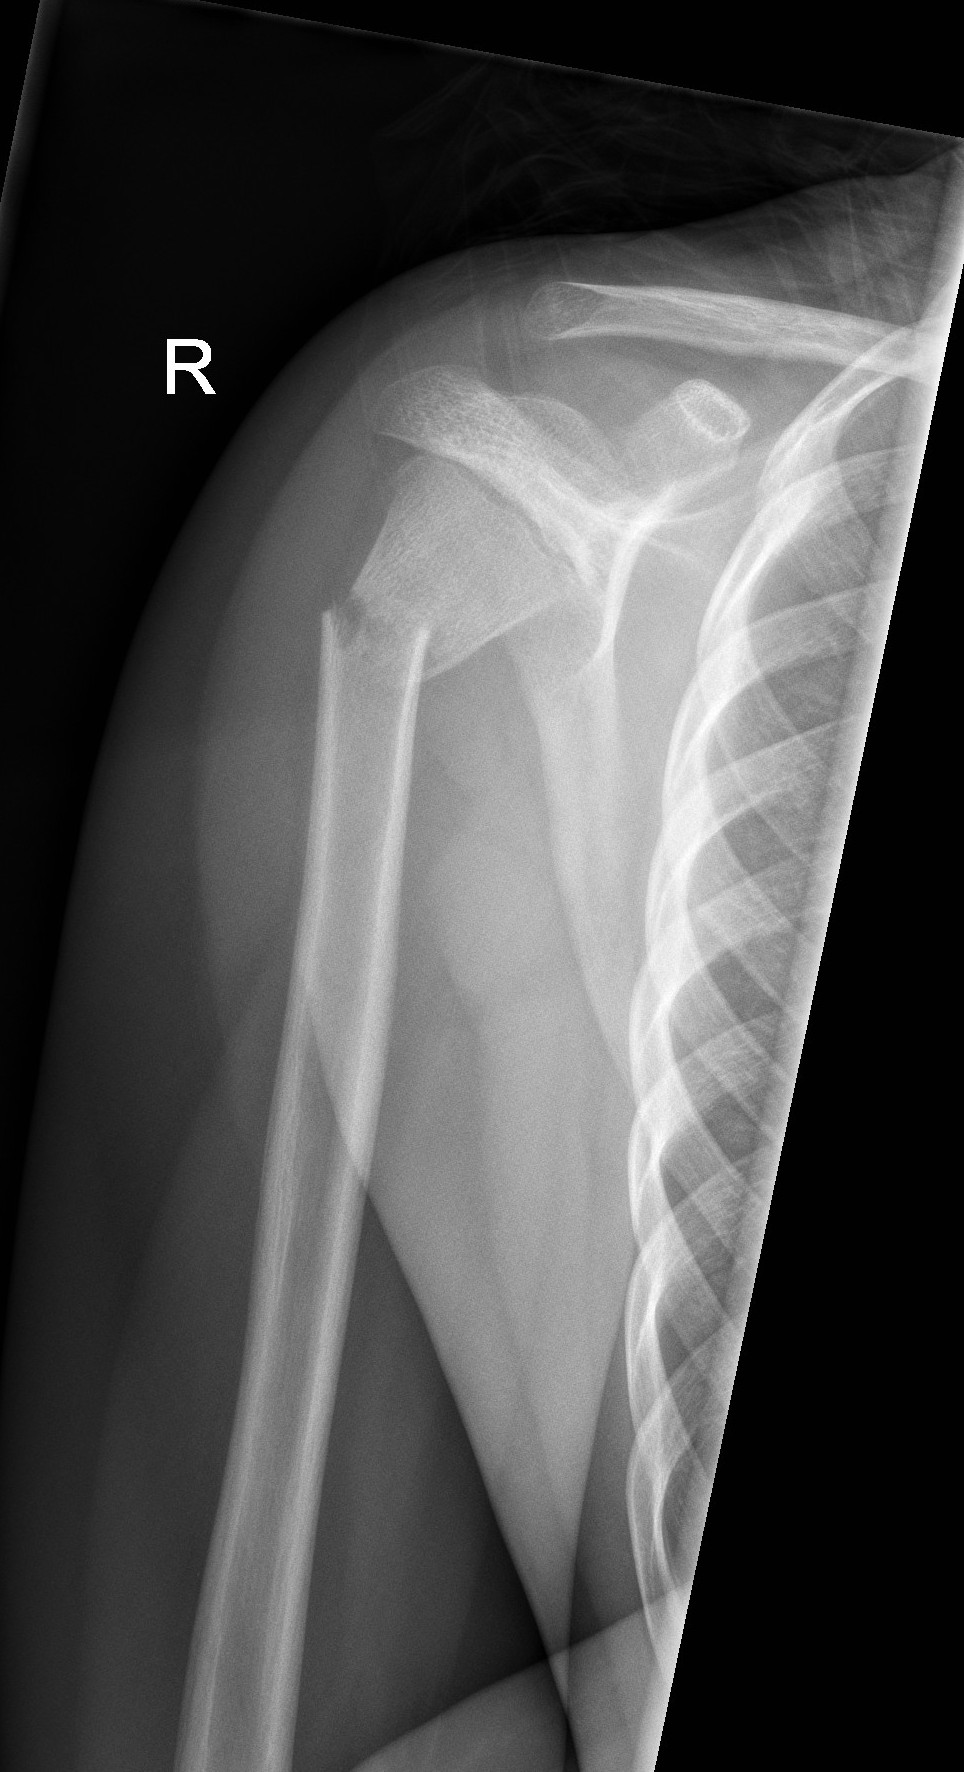

Above: Complete fracture of shaft of humerus with mild displacement

Above: Spiral fracture of shaft of humerus

Above: Completely displaced proximal humerus fracture